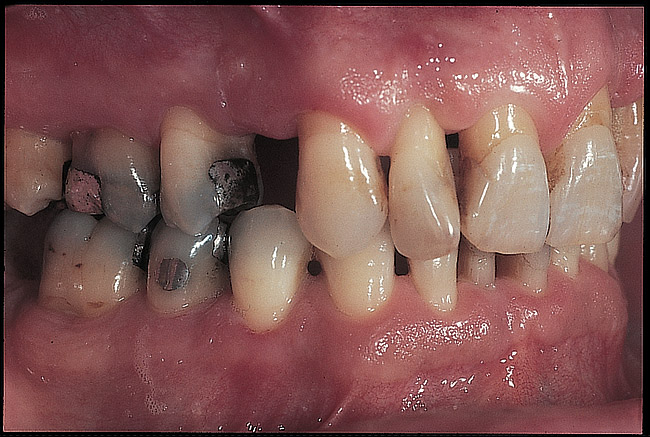

Figure 14  Preoperative intraoral view, right side.

Figure 14

Figure 15  Preoperative intraoral view, left side.

Figure 15